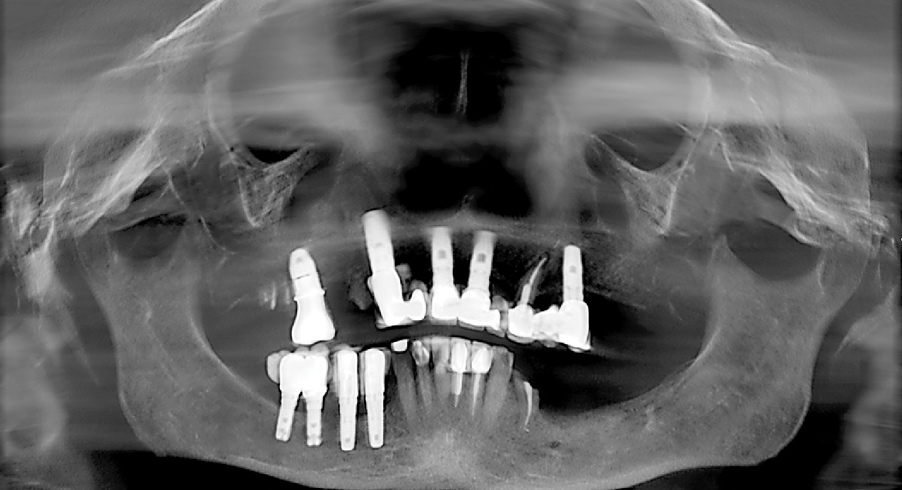

Fig 1. Presurgical panoramic radiograph of a patient with severe periodontal disease and who is an All-on-4–style treatment candidate.

Figure 1

Many patients requiring All-on-4–style treatment have extremely compromised teeth that may be unintentionally removed during the initial impression process. This is typically due to severely decayed teeth or extremely mobile teeth secondary to advanced periodontal disease (Figure 1). Such situations must be recognized and these patients advised of the potential for tooth loss during the impression process.

Removal of Dental Implants

All-on-4–style treatment sometimes requires the removal of previously placed dental implants (Figure 16 and Figure 17). Although some of these implants may have biologic complications such as peri-implantitis that may ease the removal process, most previously placed implants requiring explantation by the author have been firmly osseointegrated. Previously placed dental implants are not typically suitable for All-on-4–style surgeries because the platforms were placed to a level in accordance with the natural teeth. Although this is perfectly suitable when natural teeth are present, these platform positions are too coronal for All-on-4–style treatment. Furthermore, previously placed dental implants preclude the ability for adequate bone reduction. In the author’s experience, using previously placed dental implants for All-on-4–style treatment often results in restorations of inadequate thickness that have a propensity for fracture due to the coronal position of the platforms and the lack of bone reduction. As such, the author routinely removes previously placed dental implants when performing All-on-4–style treatment.

Fig 16. Presurgical panoramic radiograph of a patient receiving All-on-4–style treatment with multiple dental implants requiring explantation. Note the dental implants in the mandibular right quadrant that are compromising the inferior alveolar nerve.

Figure 16